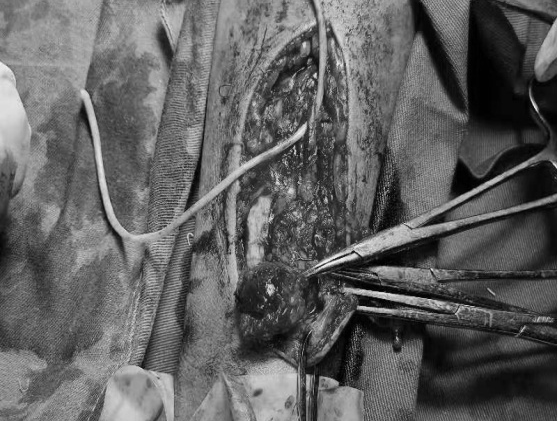

多年来,贵州航天医院各科室紧跟医学前沿,不断强技术、补短板,大力开展新技术、新项目,完成了许多高精尖、高难度、本地区“首例”的技术,填补了医院医疗技术空白,满足了群众日益增长的医疗需求。 本期,我们将为大家带来肾脏风湿科特色技术——动脉瘤、囊样扩张等切除+原位内瘘重建术。 案例分享 患者在6年前确诊尿毒症并开始进行血液透析,在入院前2天,发现右前臂出现包块,故前来我院肾内科就诊。在为患者完善了彩超等检查后,诊断为:慢性肾脏病5期,右前臂内瘘处动脉瘤形成,内瘘功能丧失。 考虑到患者曾行“冠心病+PCI术”,长期口服华法林治疗,监测凝血功能INR升高,手术中出血风险较大,在征得患者及其家属同意后,待其凝血功能INR正常后,为其实施动脉瘤切除+原位内瘘重建术。 因患者手术切口长、难度大,科室团队通过充气压脉带充气加压阻断血运,在右前臂距腕关节上约10cm处,沿动脉瘤皮肤表面纵行呈弧形切开2条长约9cm切口,内瘘吻合口静脉端见一30×20mm包块及多处小包块,经过认真,仔细的操作,最终成功为患者分离动脉瘤、脓性分泌物及坏死组织,并完成原位内瘘重建。术后,患者定期换药消毒,恢复良好。 开展动脉瘤、囊样扩张等切除+原位内瘘重建术,手术医生需经过相关专业培训,手术难度大,操作要求高。目前,贵州航天医院肾脏风湿科完全具备手术资质,已为遵义地区许多患者提供该项医疗服务,极大帮助患者节约了血管资源,减轻了因临时透析导管带来的痛苦及相关导管风险。 什么是动脉瘤、囊样扩张等 切除+原位内瘘重建术 自体动静脉内瘘是维持血液透析患者血管通路的首选方法,如果因为内瘘吻合口临近或穿刺部位形成血管瘤、囊样扩张,经过保守治疗效果不佳者,可采取动脉瘤、囊样扩张等切除,并重建动静脉内瘘。 动脉瘤、囊样扩张等切除+ 原位内瘘重建术原理 尿毒症患者动静脉内瘘术后,血液动力学的改变,经反复穿刺,导致内瘘吻合口临近或穿刺部位形成血管瘤或囊性扩张,严重时可出现动脉瘤破溃、感染等严重并发症,内瘘失功,对保守治疗效果不佳者,采取动脉瘤、囊样扩张等切除,并在原位重建动静脉内瘘。 动脉瘤、囊样扩张等切除+ 原位内瘘重建术优势 动脉瘤、囊样扩张等切除+原位内瘘重建,新内瘘成熟时间短,在短期内即可使用(约术后1周),大大提高了治疗成功率,并为患者节约血管资源。 血管通路是尿毒症维持性血液透析患者的生命线,而动脉内瘘是最重要也是最经济有效的血管通路。随着透析时间延长,部分患者内瘘血管出现动脉瘤,随时可能破裂大出血危及生命,内瘘也因此失去功能。此技术能解决内瘘动脉瘤所带来的危险,同时重建内瘘功能,对延长透析患者的生存时间,提高透析患者的生活质量具有重大意义。 贵州航天医院肾脏风湿科 专家团队 冯远军 肾脏风湿科主任 主任医师 临床擅长:对慢性肾脏病、急性肾损伤、急慢性肾小球肾炎、肾病综合症、风湿性疾病、间质性肾炎、肾小管损伤等疾病的诊治及血液透析技术、动静脉内瘘成形术及疑难病例的诊治具有丰富的临床经验。 曾在上海市第一人民医院及贵阳市第一人民医院进修学习,贵州省医学会肾脏病学分会第五届委员会委员,遵义市医学会肾脏病学分会第一届委员会副主任委员,遵义市医学会风湿病学分会第一届委员会副主任委员,荣获“贵州航天劳动模范、遵义市汇川区先进工作者”,遵义市医疗事故鉴定专家库成员,主持省市级科研项目4项,完成4项,近5年发表论文10余篇,北大核心期刊1篇。 王卫华 肾脏风湿科 主任医师 临床擅长:从事临床工作28年,擅长尿毒症患者血管通路的建设及维护(如标准和高位动静脉内瘘术、取栓+内瘘重建术、内瘘狭窄球囊扩张术、长期中心静脉置管术及肾穿刺活检术)等手术,对原发性和继发性肾病综合征、急、慢性肾小球肾炎、慢性肾脏病、泌尿系感染、结缔组织病、急性中毒、痛风、贫血、血小板减少症等疾病诊治及血液透析技术应用等具有丰富的临床经验。 1995年毕业于遵义医学院临床医学系,曾前往重庆医科大学进修学习肾脏疾病及血液净化;遵义市医学会肾脏病学分会常务委员,遵义市血液净化质量控制中心委员;先后发表肾病专业省部级医学刊物医学论文8篇,主持市级科研项目2项。 李丽华 肾脏风湿科 副主任医师 临床擅长:从事临床工作17年,对慢性肾脏病、急性肾损伤、急慢性肾小球肾炎、肾病综合征、风湿性疾病、间质性肾炎、肾小管损伤、急慢性肾衰竭的血液透析、CRRT治疗以及血管通路的建设维护等具有丰富的临床诊疗经验。 2006年毕业于遵义医学院临床专业,曾在遵义医学院附属医院完成住院医生规范化培养,并前往第三军医大学新桥医院、珠海市人民医院进修学习;中华医学会遵义市肾脏病学分会委员,遵义中医药学会肾病专业委员会委员,遵义市血液净化质量控制中心委员,遵义市医学会血液学分会委员会委员;发表省部级医学刊物医学论文4篇,主持参与省级科研课题1项,主持参与市级科研课题1项,院级新技术6项,获得本专业授权实用新型专利3项。 李 玫 肾脏风湿科 副主任医师 临床擅长:从事临床工作15年,对慢性肾脏病、急性肾损伤、急慢性肾小球肾炎、肾病综合征、风湿性疾病、间质性肾炎、肾小管损伤等疾病的诊治具有丰富的临床经验,擅长血液透析技术、动静脉内瘘成形术等。 2008年毕业于遵义医学院临床医学系,曾前往遵义医学院附属医院进修学习肾脏病与血液净化相关技术;遵义市医学会肾脏病学分会委员,发表肾病专业省部级医学刊物医学论文4篇。 贵州航天医院肾脏风湿科简介 贵州航天医院肾脏风湿科2017年建立,住院患者承载能力达到50人左右,透析治疗服务惠及250余人的患者群体,在学科建设、高端医疗设备引进及专业技术队伍已达到区域内领先水平。科室共有医护人员46名,副高级以上专家7名,亚专业设置齐全,涵盖肾脏疾病、风湿免疫疾病药物治疗、透析治疗及透析通路维护等多个专业领域,为患者提供全面、精准、高效的诊疗服务。配备了尖端的医疗设备与智能化的辅助系统,包括透析机、CRRT机等设备。 • ✦ 专科特色 ✦ • (一)肾脏病治疗领域:专精于血液透析、血液透析滤过、血液灌流、血浆置换、CRRT等尖端技术,致力于为患者量身打造个性化的肾脏替代治疗方案。 (二)在风湿病治疗方面:凭借生物制剂、免疫抑制剂等前沿药物,结合患者的具体情况,精心策划个体化的治疗策略,有效减轻患者症状,显著提升生活质量。 超声引导下球囊扩张术:内瘘狭窄是内瘘最常见的并发症之一,我们采用先进的超声引导下球囊扩张术,通过微创方式恢复内瘘通畅,有效避免了传统手术带来的创伤和痛苦。 内瘘血栓溶栓治疗、取栓术:血栓形成是内瘘功能丧失的主要原因之一,根据患者具体情况,采用溶栓治疗、取栓术等多种手段,确保患者及时恢复透析治疗。 内瘘动脉瘤形成治疗:动脉瘤是由于内瘘局部血流动力学改变引起的血管扩张性疾病,采取佩戴弹力绷带、手术修复等措施,防止动脉瘤进一步发展和破裂。 内瘘感染治疗:内瘘感染是内瘘并发症中最为严重的类型之一,一般采用敏感抗生素进行抗感染治疗,严重者采取手术清创等措施。 内瘘窃血综合征治疗:是由于内瘘建立后,远端肢体血流减少引起的一系列症状,通过调整透析方案、改善内瘘血流分布及必要时重建内瘘等措施,有效缓解患者的症状并提高其生活质量。 • ✦ 诊疗范围 ✦ • 擅长治疗急慢性肾炎、肾病综合征、肾衰竭等肾脏疾病;擅长治疗类风湿关节炎、系统性红斑狼疮、干燥综合征等风湿免疫性疾病,并为患者提供健康教育与康复指导,帮助患者更好地管理疾病,提高生活质量。